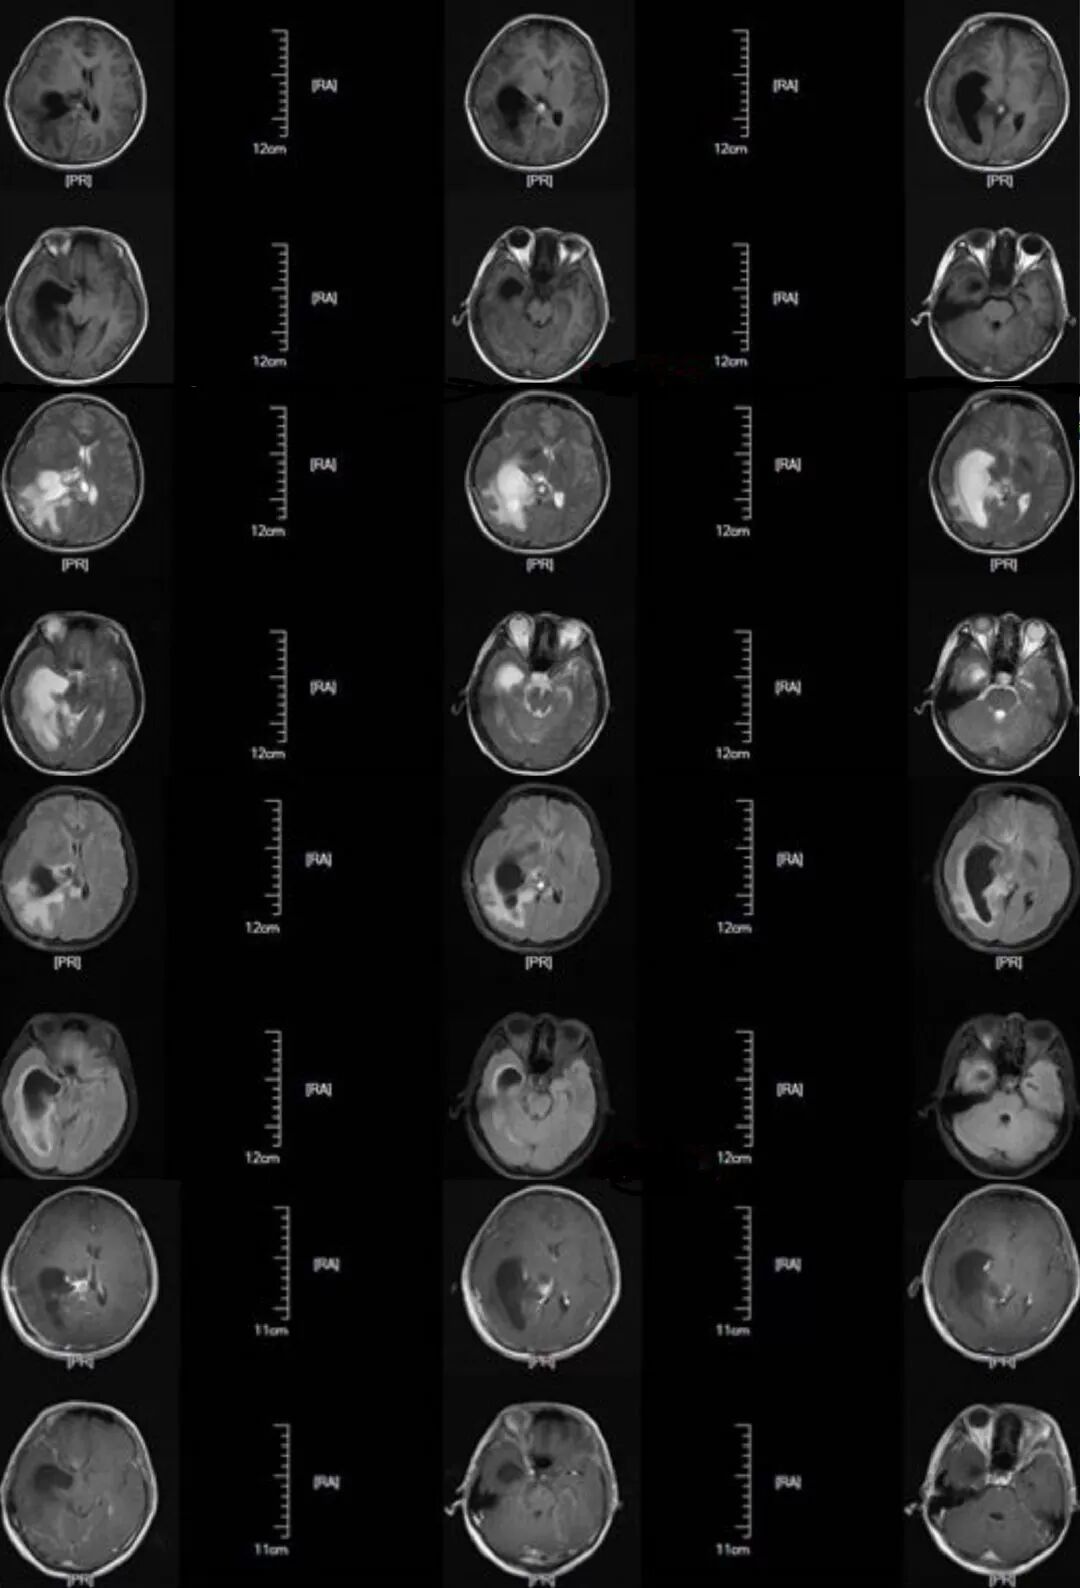

既往病史:2月余前因右侧侧脑室肿瘤,见(图1)行右侧顶枕三角区入路肿瘤切除术,术中见肿瘤呈灰白色、质地韧、血供一般,显微镜下全切除肿瘤,术后病检结果为脑膜瘤、WHOI级。

图1. 磁共振显示右侧侧脑室肿瘤,肿瘤大小约5.0 cm×6.5 cm,呈强化明显。

患者第一次肿瘤切除术后第1天复查头部CT无脑积水,于术后第4天拔出脑室外引流管,术后第14天复查头部MRI无异常(图2),后出院。术后第48天患者常规复查头部MRI(图3)提示右侧侧脑室颞角、后角扩张并周围脑组织水肿、中线轻度移位,由于患者无明显颅高压症状,予以观察并定期复查。患者于术后第62天开始出现头痛,恶心,在当地医院行甘露醇脱水治疗,治疗后症状稍改善,但停用脱水药物时患者头痛恶心呕吐症状就再出现。

图2. 术后第14天复查头部MRI无异常。

图3. 术后第48天患者常规复查头部MRI,提示右侧侧脑室颞角、后角扩张并周围脑组织水肿、中线轻度移位。

患者于术后第64天再次入院,入院后行头部MRI(图4)检查提示右侧侧脑室颞角、后角扩张并周围脑组织水肿、中线明显移位,并行腰穿测压为280cmH2O,诊断为右侧侧脑室三角区脑膜瘤切除术后孤立颞角综合征,遂于术后第68天行侧脑室颞角腹腔分流术,分流管为美敦力可调压力分流管,术中设定压力范围为105~125mmH2O,术后复查头部CT以及MRI(图5、6)。

图4. 磁共振检查提示右侧侧脑室颞角、后角扩张并周围脑组织水肿、中线明显移位。

图5. 显示V-P分流术后复查头部CT。

图6.显示V-P分流术后复查头部MRI。